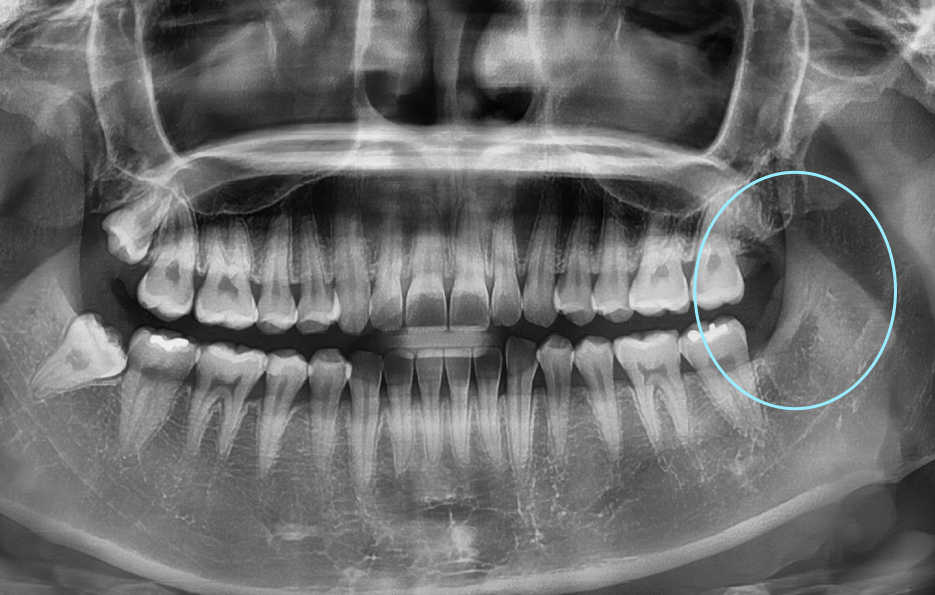

위 환자분의 사랑니 케이스를 살펴보면 윗니의 경우 정상 맹출된 사랑니의 형태를 보이지만 아랫니의 경우에는 부분 매복되어 있고 누워서 자라고 있는 사랑니의 형태를 볼 수 있어요. 다 그런 것은 아니지만 윗니의 경우 중력에 의해 정상 맹출된 사랑니의 형태가 좀더 많다면 아랫니의 경우 매복사랑니의 형태가 많은 편이기 때문에 하악 사랑니의 발치가 좀더 어려운 경우가 있어요

부분매복 사랑니는 이렇게 문제가 생겨요

부분적으로 맹출된 사랑니는 어금니와 사랑니 사이에 음식물이 끼기 쉽고 어금니 인접면에 사랑니로 인한 충치가 발생되기도 쉬우며 심한 경우에는 어금니의 뿌리 쪽 손상을 일으켜서 신경치료나 발치까지도 이르게 되는 경우가 있기 때문에 사랑니 발치 시점을 놓치게 되면 어금니 손상까지 커질 우려가 있어요